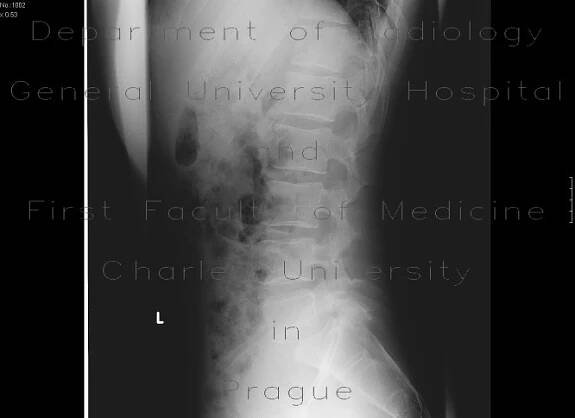

Spina bifida (SB; / ˈ s p aɪ n ə ˈ b ɪ f ɪ d ə/; [9 ] Latin for 'split spine') [10 ] is a birth defect in which there is incomplete closing of the spine and the membranes around the spinal cord during early development in pregnancy. [1…

Rozštěp páteře (spina bifida) je vada v oblasti páteře a míchy, která vzniká na začátku těhotenství. Typy a příznaky spiny bifidy se mohou značně lišit. Na tom pak do značné míry závisí úspěšná léčba pomůckami, jako jsou ortézy.

Spina bifida, někdy též obecně označovaná jako „rozštěp páteře“, je vrozená vada (VV) CNS ze skupiny rozštěpů neurální trubice (neural tube defects; NTD).

Spina bifida , často nazývaná rozštěp páteře, je vrozená vada, která se vyskytuje, když páteř není úplně uzavřená během embryonálního vývoje.